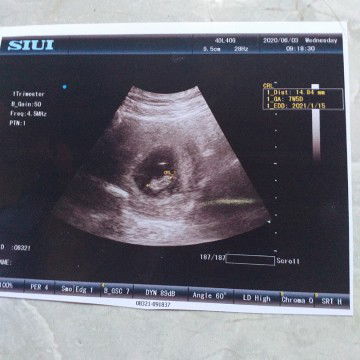

USG

Ini hasil USG Q hari ini bund,, dan alhamdulillah sudah ada janinnya n detak jantungnya bund, hamil 7w5d bund,,,, ??